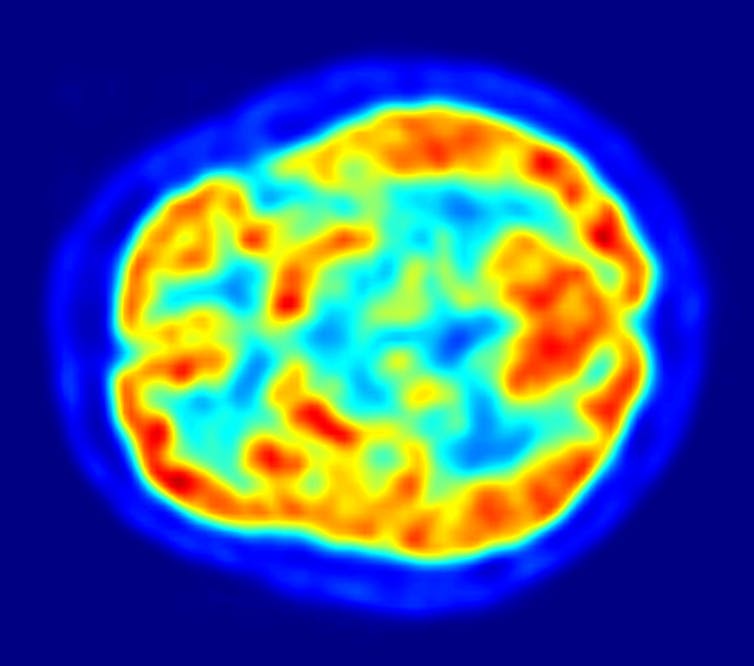

Every year we use a supercomputer to analyse vast amounts of measurements from satellites and field stations to give the condition of Australia’s environment a score out of ten. For 2021, we score it 6.9 – four points higher than the year before.